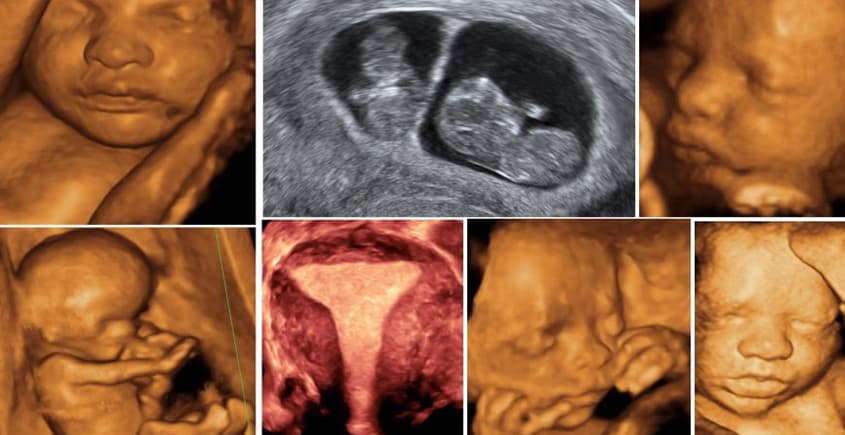

Gebeliğin 18-23. haftaları arasında yapılan, bebeğin tüm organlarının (beyin, kalp, böbrekler, eller, ayaklar vb.) detaylı olarak incelendiği radyolojik değerlendirmedir.

Ayrıntılı ultrason muayenesi bebeğin organlarındaki sakatlıkları saptadığı gibi Down sendromu gibi kromozom bozuklarının bazı belirtilerini de saptayabilir.

- Kafatası ve beyin yapısı

- Yüz profili, dudak ve damak yapısı

- Omurganın gelişimsel bozuklukları (örn: bel-de açıklık, kemiklerde eğrilik veya eksiklik vs.)

- Göğüs ve karın boşluğuna ait sakatlıklar (örn: iç fıtık, dış fıtık, akciğer ve karaciğer problemleri, mide ve bağırsaklara ait problemler, böbrek ve idrar kesesine ait problemler vs.)

- Yüze ait sakatlıklar (örn: göz boşluğunun olmaması, yüzdeki yarıklar, dudak yarıkları vs.)

- El ve ayaklardaki kemik sayıları ve şekil bozukluğu (kol ve bacak kemiklerinde eksiklik, elde ve ayakta içe-dışa dönüklük vs.)

- Bebeğin içinde bulunduğu suya ve plasentaya (eş) ait problemler (suyun azalması veya artması, plasentanın anormal yerleşimi vs.)

- Bebek kalbinin belirgin yapısal gelişim bozuklukları.